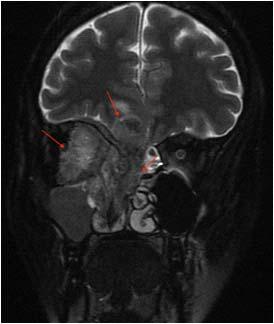

Spontaneous or acute ICH appears on the CT head as an area of hyperdensity within the Parenchyma (Fig 2) or extended into the ventricle (Fig 3), with surrounded hypodense perivascular oedema.

Fig 3 — Non-contrast axial image of head CT showing acute intracranial haemorrhage involving the left thalamus and basal ganglia(white arrow) with extension into the ventricle. (black arrow)